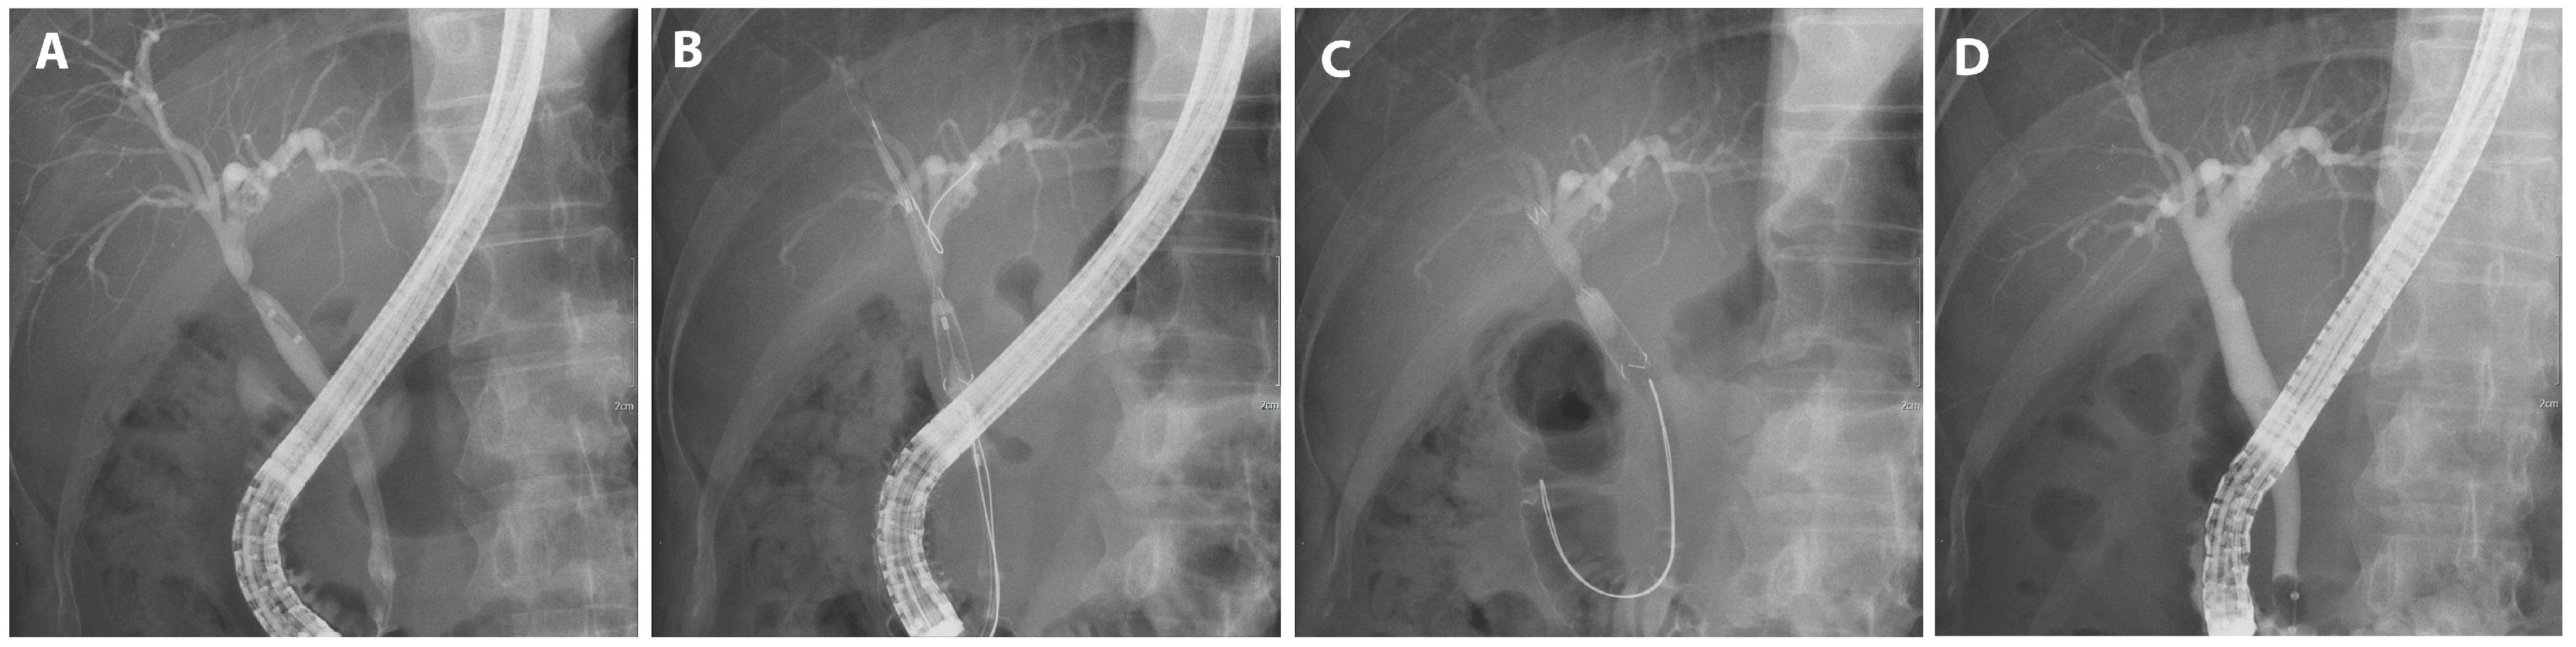

Each endoscopic retrograde cholangiopancreatograph (ERCP) was performed by one of five experienced endoscopists, each with more than five years of experience and more than 1000 successful ERCPs. Throughout the intervention, patients were given a sedative regimen comprising propofol, midazolam, and pethidine while being continuously monitored either by an anesthesiologist or the performing endoscopist. The procedure was performed using duodenoscopes (TJF-260 and TJF-290V; Olympus Medical Systems Corp., Tokyo, Japan) equipped with a 4.2 mm instrument channel, ensuring precise diagnosis and therapeutic intervention. After bile duct cannulation, a guide wire was inserted through the stricture. The stenosis length and the diameter of the proximally dilated intrahepatic duct, as discerned on the cholangiogram, informed the choice of stent dimension, ensuring comprehensive coverage of the stenotic segment (Figure 2A). The placement of the stent was carefully adjusted to ensure the alignment of its central radiopaque marker with the site of the stenosis (Figure 2B). In cases of severe stenosis that hindered catheter insertion, either a balloon dilator (6 mm or 8 mm, Hurricane RX; Boston Scientific, Marlborough, MA, USA) or a bougie dilator (Soehendra Biliary Dilation Catheter; Cook Medical, Bloomington, IN, USA) was used as a preliminary intervention. The stent body was placed inside the bile duct, and the retrieval string was pulled out of the papilla and positioned in the duodenum. Each short FCSEMS was retained for 3 months before being meticulously extracted using endoscopic forceps. Then, cholangiography was undertaken to verify rectification of the BBS (Figure 2D). To ward off potential infections, prophylactic antibiotics were judiciously administered both pre- and post-procedure.

Figure 2.

FCSEMS treatment of biliary anastomotic stricture after cholecystectomy. A case of biliary anastomotic stricture diagnosed after cholecystectomy and treated with FCSEMSs is presented. (A) A biliary anastomotic stricture that had developed after surgery was observed in the common bile duct on cholangiography. (B) The stent was positioned before deployment such that the central radiopaque marker was aligned with the stenosis. (C) An FCSEMS (6 mm in diameter, 4 cm in length; KAFFES) was deployed at the site of biliary anastomotic stricture. (D) After 9 months of FCSEMS use, including two replacements, the stent was removed, and the procedure was terminated after confirming that the biliary anastomotic stricture had resolved.

We treated 75 patients with BBS using short FCSEMSs. The mean age of the participants was 58.3 years; 55 were male and 20 were female. The most common surgery performed on these patients was cholecystectomy, accounting for 41.3% (31 of 75) of patients. This was followed by DDLT, which accounted for 30.7% (23 of 75) of patients. Liver resection was performed in 20.0% (15 of 75) of patients. The remaining 8.0% (6 of 75) of patients were diagnosed with benign strictures. In this study, we presented procedural images of representative cases by cause. A patient who underwent a therapeutic ERCP procedure for biliary stricture following cholecystectomy, a major cause of BBS independent of LDLT, experienced recovery after 9 months of FCSEMS treatment, including two replacement procedures (Figure 2).